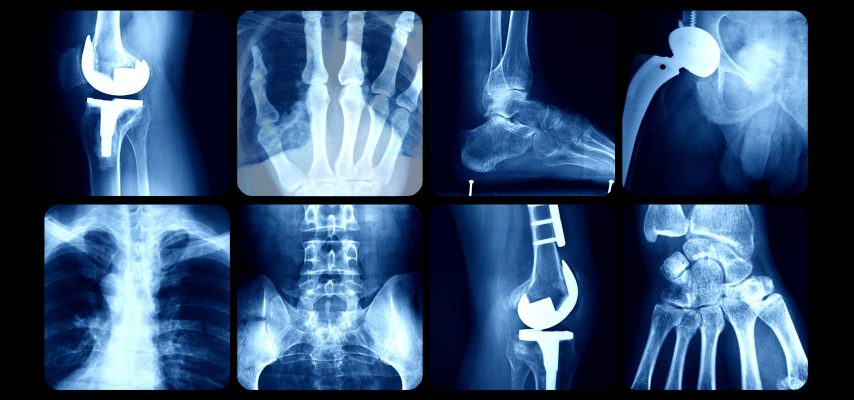

Orthopaedic surgeries: Why Nigerians should no longer travel abroad

Dr Mohammed Salihu, Medical Director, National Orthopaedic Hospital Dala (NOHD), Kano, says the hospital now receives patients from aboard for joint replacement, spine surgeries and other specialized orthopaedic surgeries.

“We can do most of the surgeries that people go outside the country to do, particularly joint replacement; we also do hip and knee replacement, as well as spine surgeries.

“ The hospital also has new sub-areas with surgeons, who can open up the patient’s back and straighten it and get them back to walk; we opened up that newly, it was not there before.

“For me, I will say that for any Nigerian to say he is going abroad for treatment of joint replacement and spine surgeries it is no longer necessary.